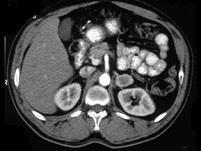

问题 女,34岁,无意中发现血压升高4 个月就诊,行CT检查,如图所示,下列说法正确的是 ( )

选项 A、考虑为左肾上腺嗜铬细胞瘤 B、考虑为左肾上腺转移瘤 C、增强扫描,该病灶周边明显强化,中心处强化不明显 D、考虑为左肾上腺腺瘤 E、CT示左侧肾上腺区可见一等密度块影,边界清楚

答案 ACE